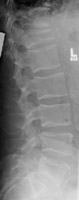

Compression fractures of the spine are common in elderly and osteoporotic patients. They result from anterior or lateral flexion. The typical appearance is loss of height of the anterior aspect of the vertebral body with preservation of the posterior elements and generally the posterior aspect of the vertebral body. On the frontal view, there may be subtle deviation of the paraspinous line due to edema. Differentiation from a pathologic fracture of the spine due to a metastasis is usually of clinical concern, but simple compression fractures are usually due to osteoporosis.

- Click on the image for a larger versionBAP radiograph of the lumbar spine. This shows loss of height of the L1 vertebral body, corresponding to a compression fracture.